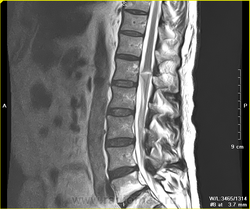

Интересно. На грудном уровне операцию делали?

Здесь полный перерыв спинного мозга в обоих случаях?

Делали декомпрессию. Видны дефекты дуги Th5, рубцовые изменения в мягких тканях спины.

Похоже, что так. Первый сам передвигаться не может. Второй ходит с большим трудом. У обоих тазовые нарушения.